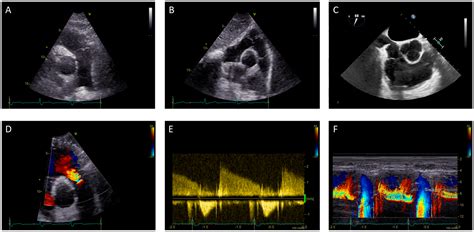

• Echocardiogram: This ultrasound test provides detailed images of the heart and can detect the presence and severity of regurgitation.

• Cardiac Magnetic Resonance Imaging (MRI): This advanced imaging technique can provide detailed images of the heart and its valves, helping to assess the severity of regurgitation.